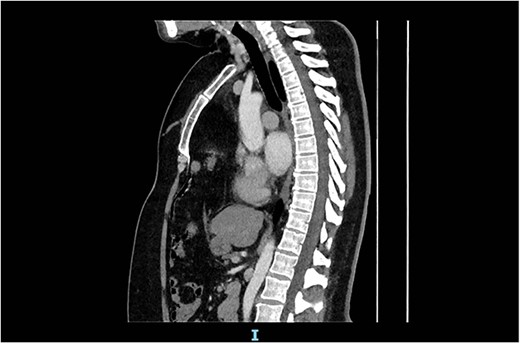

Arterial contrast CT of the chest. Sagittal slice in the midline of the body. The diaphragmatic defect is clearly seen anteriorly, and the abdominal contents are seen extending to the superior mediastinum.